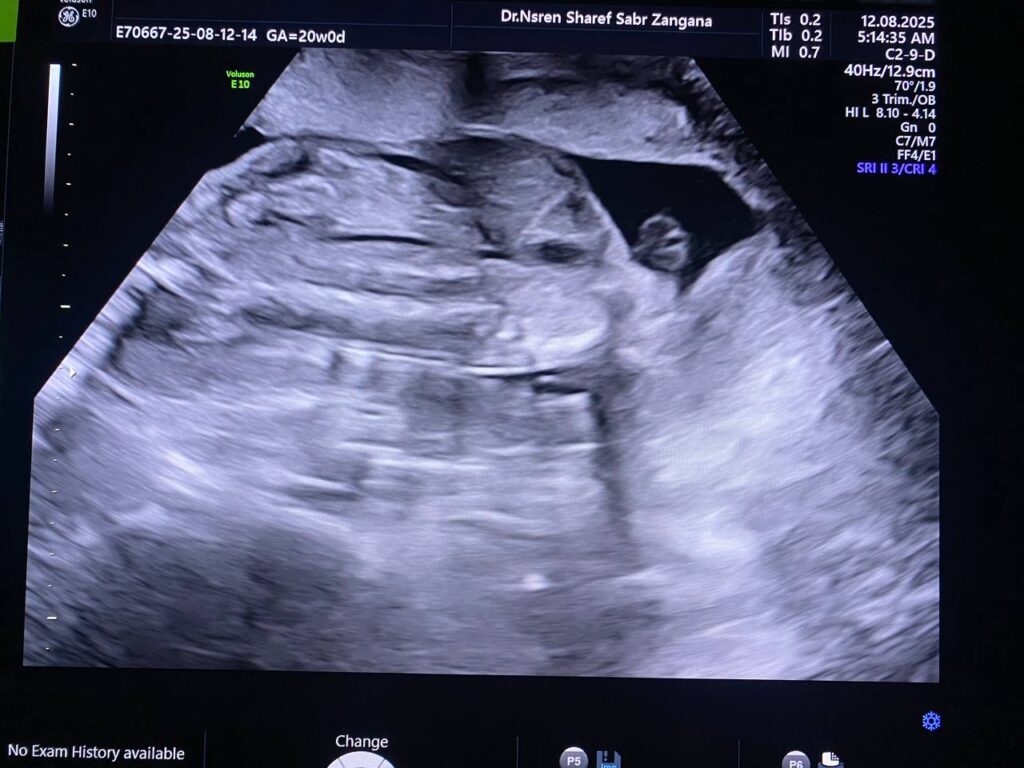

Multiple congenital anomaly seen , small chest , curve long bones , short limbs , kyphoscoliosis, congenital heart disease , edematous skin, picture mostly of thanatophoric dysplasia

F.L. = 16w+2d